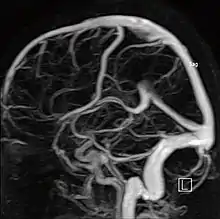

МР-ангиография

Магнитно-резонансная ангиография (МР-ангиография, МРА) — метод получения изображения кровеносных сосудов при помощи магнитно-резонансного томографа. Исследование проводится на томографах с напряжённостью магнитного поля не менее 0.3 Тл. Метод позволяет оценивать как анатомические, так и функциональные особенности кровотока.

Ангиография артерий головного мозга (времяпролетная ангиография)